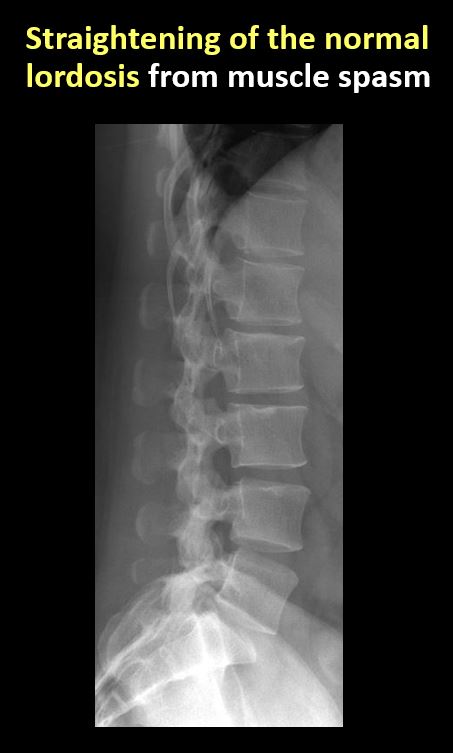

There is reversal or straightening of the normal lordosis or scoliosis of the lumbar spine. |